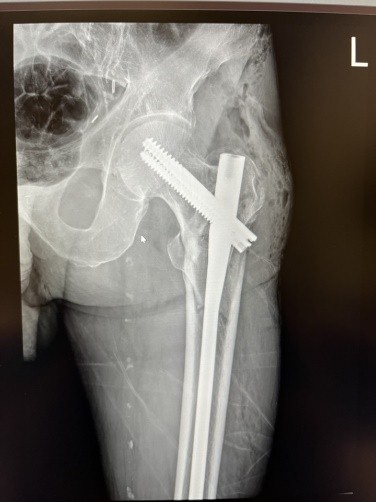

The computed tomography trauma series revealed vertebral osteoporotic fractures of TH12, L1, and L3, which are not related to the acute trauma. He was given adequate painkillers, immobilized with a coxo-femoral cast bilaterally, and was admitted to the intensive care unit. After a short pre-operative preparation, he underwent operative treatment for both fractures on the day of admission, which was performed under general anesthesia. The patient was placed on a radiolucent traction table, and the right transtrochanteric fracture was first fixated with closed reduction and a non-reamed intramedullary short nail. After open reduction, the left subtrochanteric fracture was fixated with a non-reamed long nail with distal static locking screws. Fluoroscopic image controls were acceptable, and there were no intraoperative complications. Postoperatively, patient recovery was without complications; the only problem was non-complicated anemia (67 g/L), solved with two units of blood. On the 1st post-operative day, radiographic control was done (Figs. 2 and 3).

Figure 3: First post-operative day radiographic control of the left hip. Open reduction and intramedullary fixation (InterTan 10×400).